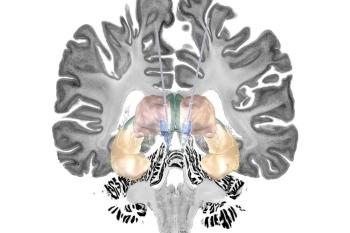

Die Alzheimer-Krankheit ist die häufigste Ursache von Demenzerkrankungen, bislang aber nicht gut behandelbar. Eine mögliche zukünftige Therapieform könnte die sogenannte Tiefe Hirnstimulation sein, die auch als Hirnschrittmacher bekannt ist.